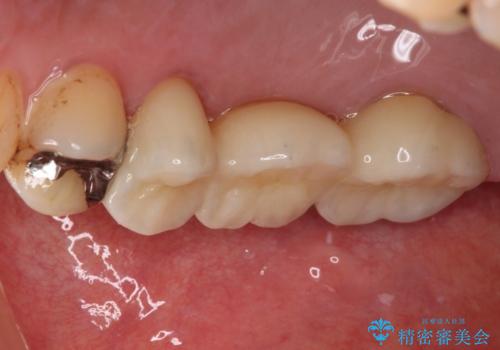

虫歯が大きく進行していましたが、歯髄(神経組織)にまで及ぶものではなかったため、無事に虫歯治療を行うことができました。

歯石もしっかりと除去したことで、周辺の腫れていた歯肉も引き締まり、健全な状態となりました。